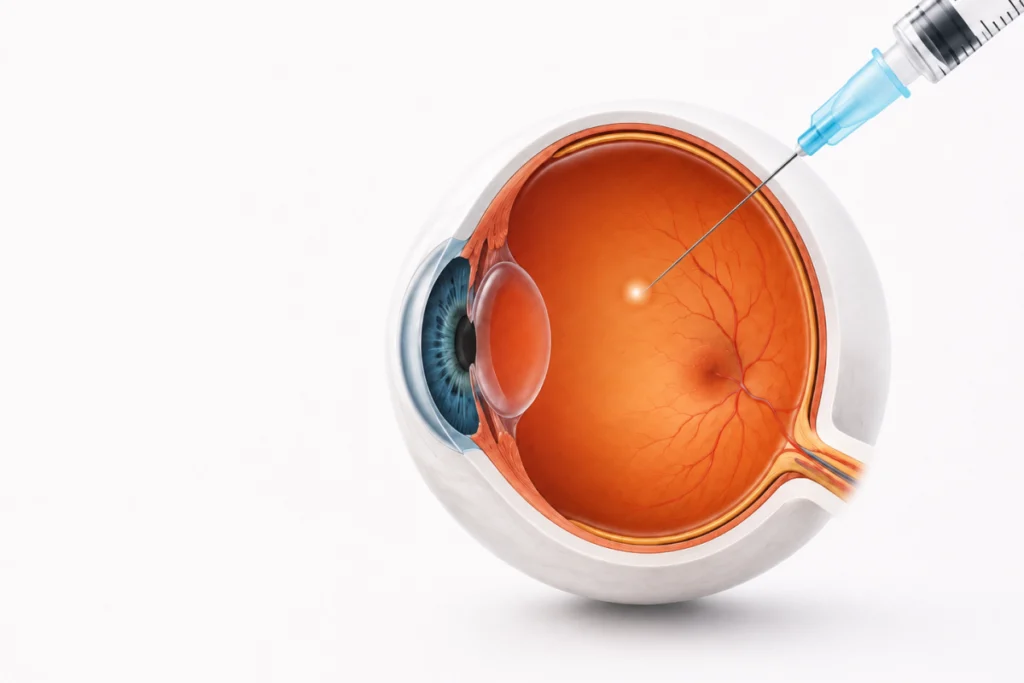

Du diagnostic à la chirurgie, le cabinet propose une prise en charge complète des principales pathologies oculaires : cataracte, chirurgie réfractive, chirurgie des paupières, traitements laser et médecine esthétique du regard.